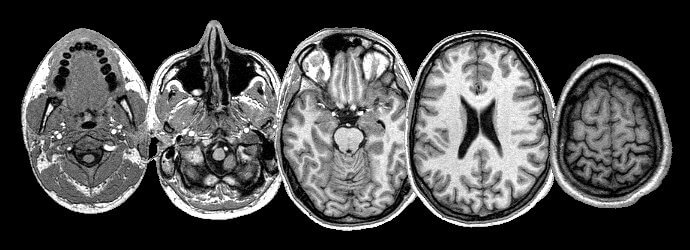

Physicians can now call on a range of techniques to see inside the body of their patients. X-rays, discovered by Roentgen, were the first but now sophisticated computer technology allows surgeons to plan operations and radiologist to target tumours with pinpoint accuracy. Ultrasound, magnetic resonance imagery (MRI), Positron Emission Tomography (PET) and computer tomography (CT) scans are all part of the doctor's diagnostic armoury.

Five MRI images of a human head